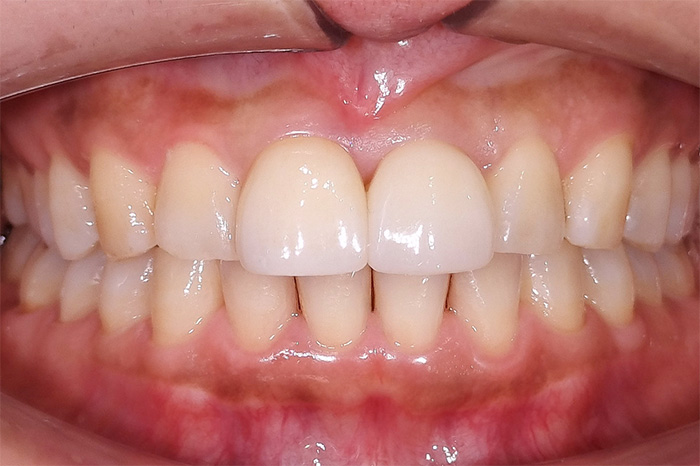

下の前歯の変色に対して、オフィスホワイトニングを行った症例

こちらの患者様は、下の前歯の色の変化を気にされて来院されました。診査の結果、上の前歯にはすでにセラミック修復が行われており、下の前歯は天然歯の状態でした。

ホワイトニングでは、天然歯は白さの変化が期待できますが、セラミックなどの人工歯は基本的に白くなりません。

本症例では、オフィスホワイトニングを1回行い、天然歯である下の前歯に色調の改善がみられました。

ホワイトニングを検討される際には、天然歯と人工物が混在しているかどうかで、仕上がりの見え方が変わることがあります。

当院では、現在の歯の状態を確認したうえで、ホワイトニングが適しているか、あるいは被せ物の再治療を含めた方法がよいかを丁寧にご提案しています。

Before

After

下の前歯の変色に対して、オフィスホワイトニングを1回行った症例です。

上顎前歯のセラミックには色調変化はありませんが、天然歯である下顎前歯には白さの改善がみられました。

下顎前歯部の着色・変色

上顎前歯部には既存のセラミック修復物を認める状態

下の前歯の色調改善を目的に、オフィスホワイトニングを1回行いました。

上の前歯はすでにセラミックで治療されていたためホワイトニングによる色調変化はありませんでしたが、天然歯である下の前歯には色調の改善がみられました。